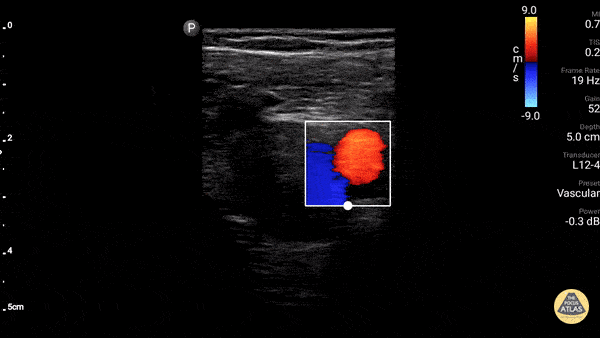

Name the vessel with the Red color in this scna of the left side of the neck:

Carotid